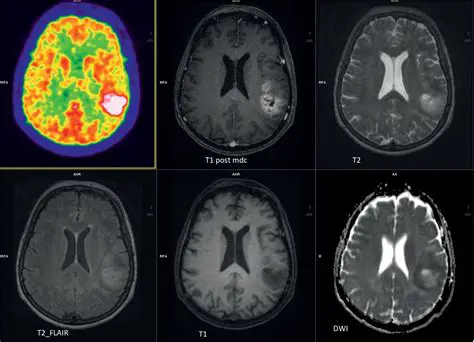

Benefits of MRI in Diagnosing Brain Tumors